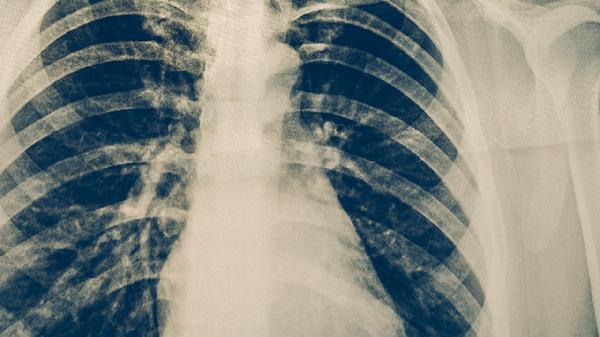

存在肺部结节、肺结核、肺癌等肺部疾病的患者可以遵医嘱使用清肺散结丸。建议及时就医,积极配合医生治疗,在医生的指导下服用合适的药物,并做好饮食调理。

清肺散结丸可用于肺部结节患者。肺部结节是指肺部出现的小于3厘米的圆形或类圆形病灶,可能由感染、炎症或肿瘤引起。清肺散结丸具有活血化瘀、软坚散结的作用,有助于改善肺部微循环,促进结节吸收。但需注意,肺部结节的性质需通过影像学和病理检查明确,恶性结节需结合其他治疗手段。

清肺散结丸适用于肺结核患者辅助治疗。肺结核是由结核分枝杆菌引起的慢性传染病,常表现为咳嗽、咯血、低热等症状。该药能缓解结核病灶周围的炎症反应,减轻纤维化,但必须与抗结核药物联合使用,单独使用无法杀灭结核杆菌。治疗期间需定期复查肝功能。

清肺散结丸可作为肺癌患者的辅助用药。肺癌是肺部恶性肿瘤,早期症状隐匿,晚期可能出现咳血、胸痛等。该药通过抑制肿瘤细胞增殖、增强免疫功能发挥辅助作用,但不能替代手术、放疗或化疗等主要治疗手段。使用期间需密切监测肿瘤标志物变化。

清肺散结丸对慢性支气管炎有一定改善作用。慢性支气管炎是气管、支气管黏膜及其周围组织的慢性非特异性炎症,主要表现为反复咳嗽、咳痰。该药能减轻气道炎症,促进痰液排出,但急性发作期需配合抗生素治疗。长期吸烟者应同时戒烟。

清肺散结丸对肺纤维化患者可能有益。肺纤维化是以成纤维细胞增殖及大量细胞外基质沉积为特征的间质性肺疾病,表现为进行性呼吸困难。该药可抑制纤维母细胞活化,延缓肺功能下降,但需与糖皮质激素等药物联合使用。严重缺氧患者需氧疗支持。